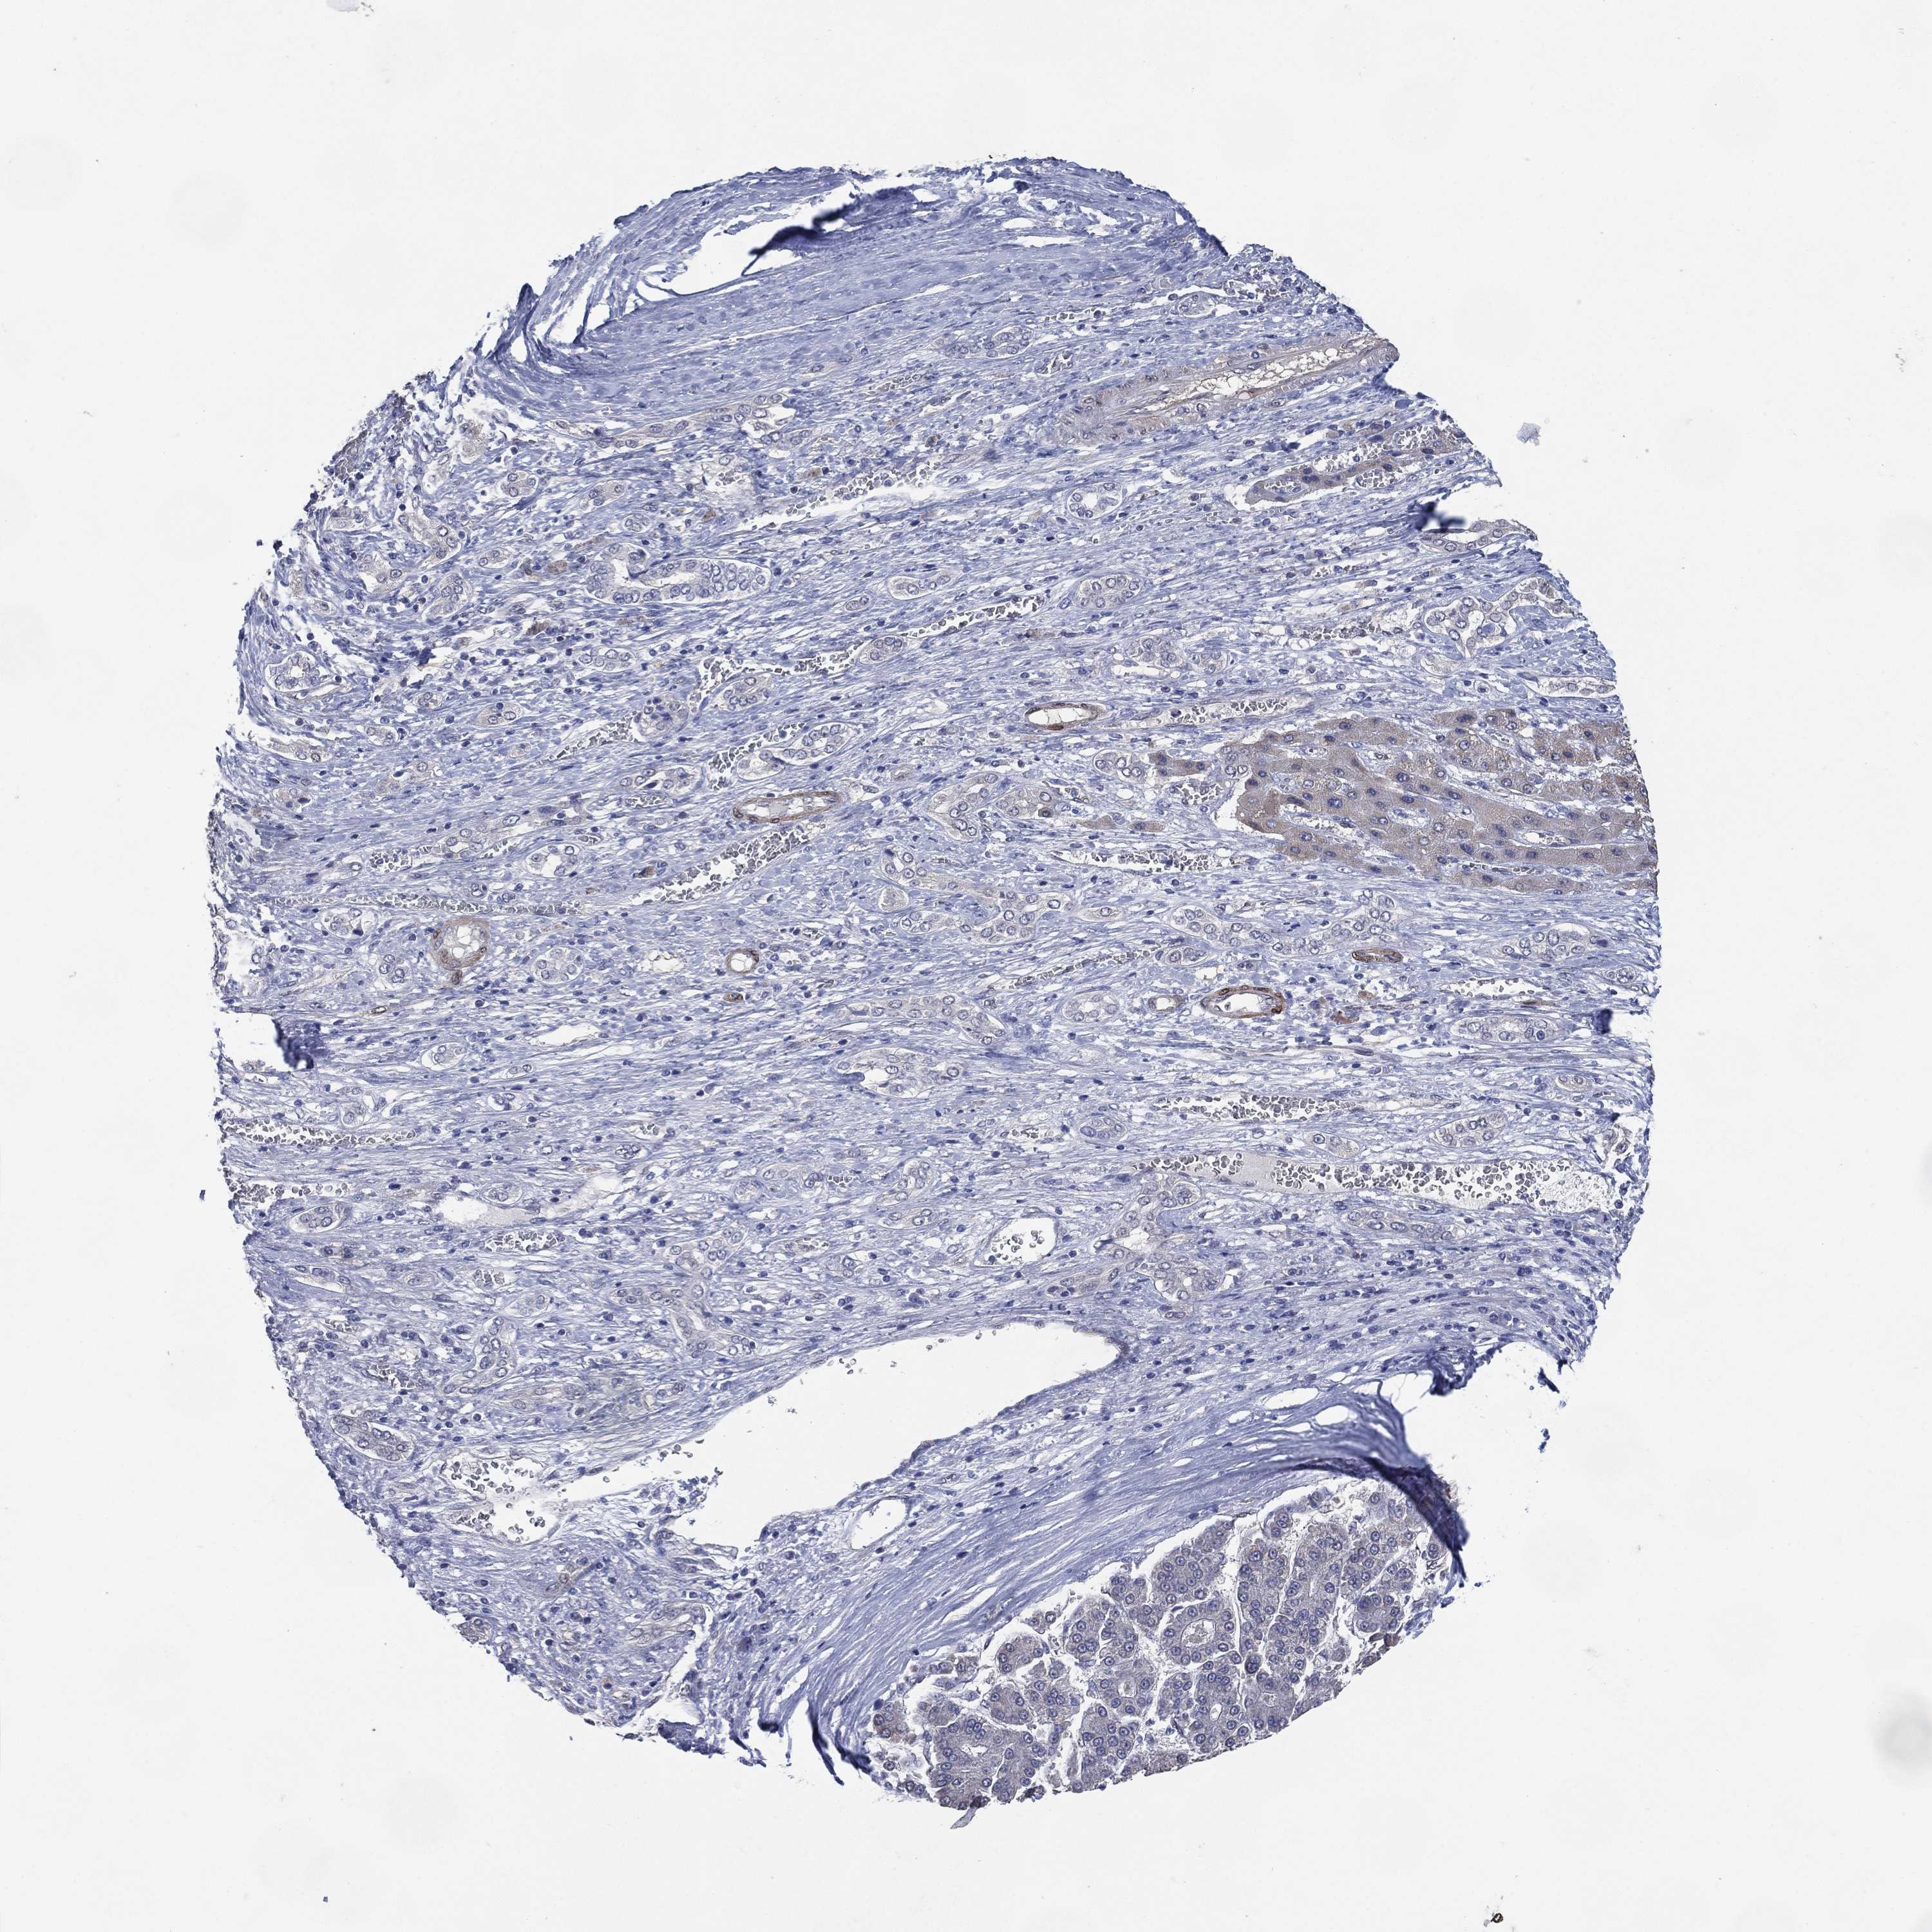

LIVER CANCER - Protein expressioni

A mouse-over function shows sample information and annotation data. Click on an image to view it in a full screen mode. Samples can be filtered based on level of antibody staining by selecting one or several of the following categories: high, medium, low and not detected. The assay and annotation is described here.

Note that samples used for immunohistochemistry by the Human Protein Atlas do not correspond to samples in the TCGA dataset.

Antibody stainingi

Antibody staining in the annotated cell types in the current human tissue is reported as not detected, low, medium, or high, based on conventional immunohistochemistry profiling in selected tissues. This score is based on the combination of the staining intensity and fraction of stained cells.

Each image is clickable and will lead to virtual microscopy that enables deeper exploration of all samples and also displays staining intensity scores, fraction scores and subcellular localization as well as patient and tissue information for each sample.

Antibody HPA006456

Antibody CAB009893

Staining

High

Medium

Low

Not detected

Intensity

Strong

Moderate

Weak

Negative

Quantity

>75%

75%-25%

<25%

None

Location

Nuclear

Cytoplasmic/membranous

Cytoplasmic/membranous,nuclear

Carcinoma, Hepatocellular, NOS

Cholangiocarcinoma

Adenocarcinoma, NOS